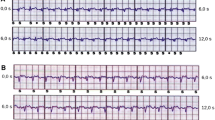

Consecutive patients who were undergoing invasive electrophysiological studies on clinical grounds were recruited. Every recruited participant was fitted with a seven-lead, three-channel Holter device prior to their clinical procedure. The leads for the Holter device were placed in a way such as the three recorded channels corresponded to the three distinct sensing vectors of an S-ICD, namely primary (from proximal electrode ring to can), alternate (from distal to proximal electrode), and secondary (from distal electrode ring to can) vectors, see Fig. 1. At the beginning or towards the end of the clinically indicated electrophysiology procedure, at the discretion of the operator, the right ventricle was paced at four different locations—true apex, apical septum, mid septum, and high septum—for 10 beats at each position at the same rate (10 beats above the resting heart rate) and using the same parameters (8 mA/2 ms) for all the paced beats. The positions of the pacing catheter were confirmed by the operator using multiple fluoroscopic views, see Fig. 2. The pacing impulses were delivered using a standard conventional pacing catheter to mimic the pacing impulses that would be delivered by a pacemaker. The four different pacing locations that were chosen for the study were based on the most common leadless pacemaker implantation sites reported in the Micra post approval registry [11].

Showing the typical S-ICD vectors on the left and on the right, the Holter® surface ECG positions. 1 = 1 cm infero-lateral to the xiphisternum, 2 = 14 cm superior to position 1, 3 = 5th intercostal space, parasternal position, 4 = 6th intercostal space left mid axillary line, 6 = Adjacent to 2, 7 = Adjacent to 4, Holter Channel A records between points 1 and 4 = surrogate of S-ICD primary vector, Holter Channel B records between points 2 and 3 = surrogate of S-ICD alternate vector, Holter Channel C records between points 6 and 7 = surrogate of S-ICD secondary vector, 5 = 5th intercostal space right mid clavicular line = neutral electrode, Image prior to annotation